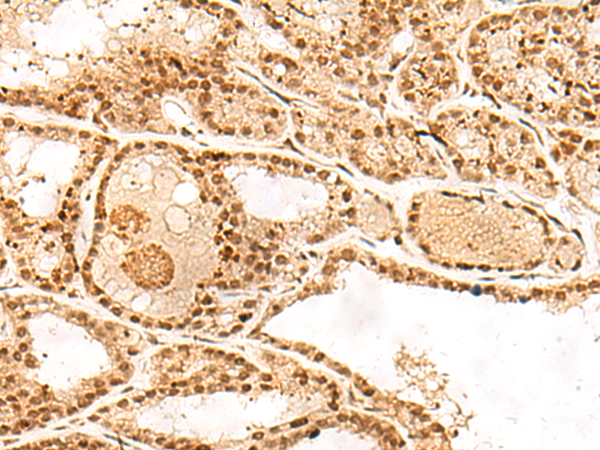

分类: 科研抗体货号: P02908别名: AGS3应用: WB,IHC反应种属: Human, Mouse, Rat